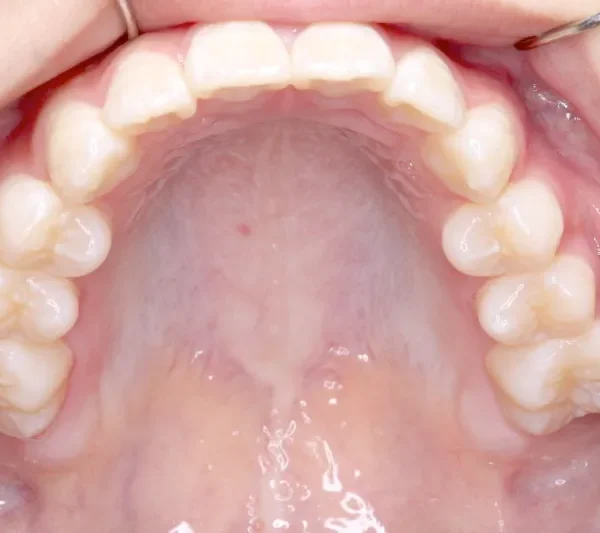

• 治療終了後

治療終了後

治療回数43回、7年4ヶ月の治療期間で矯正治療を終了しました。

主訴が改善され、ご満足頂きました。